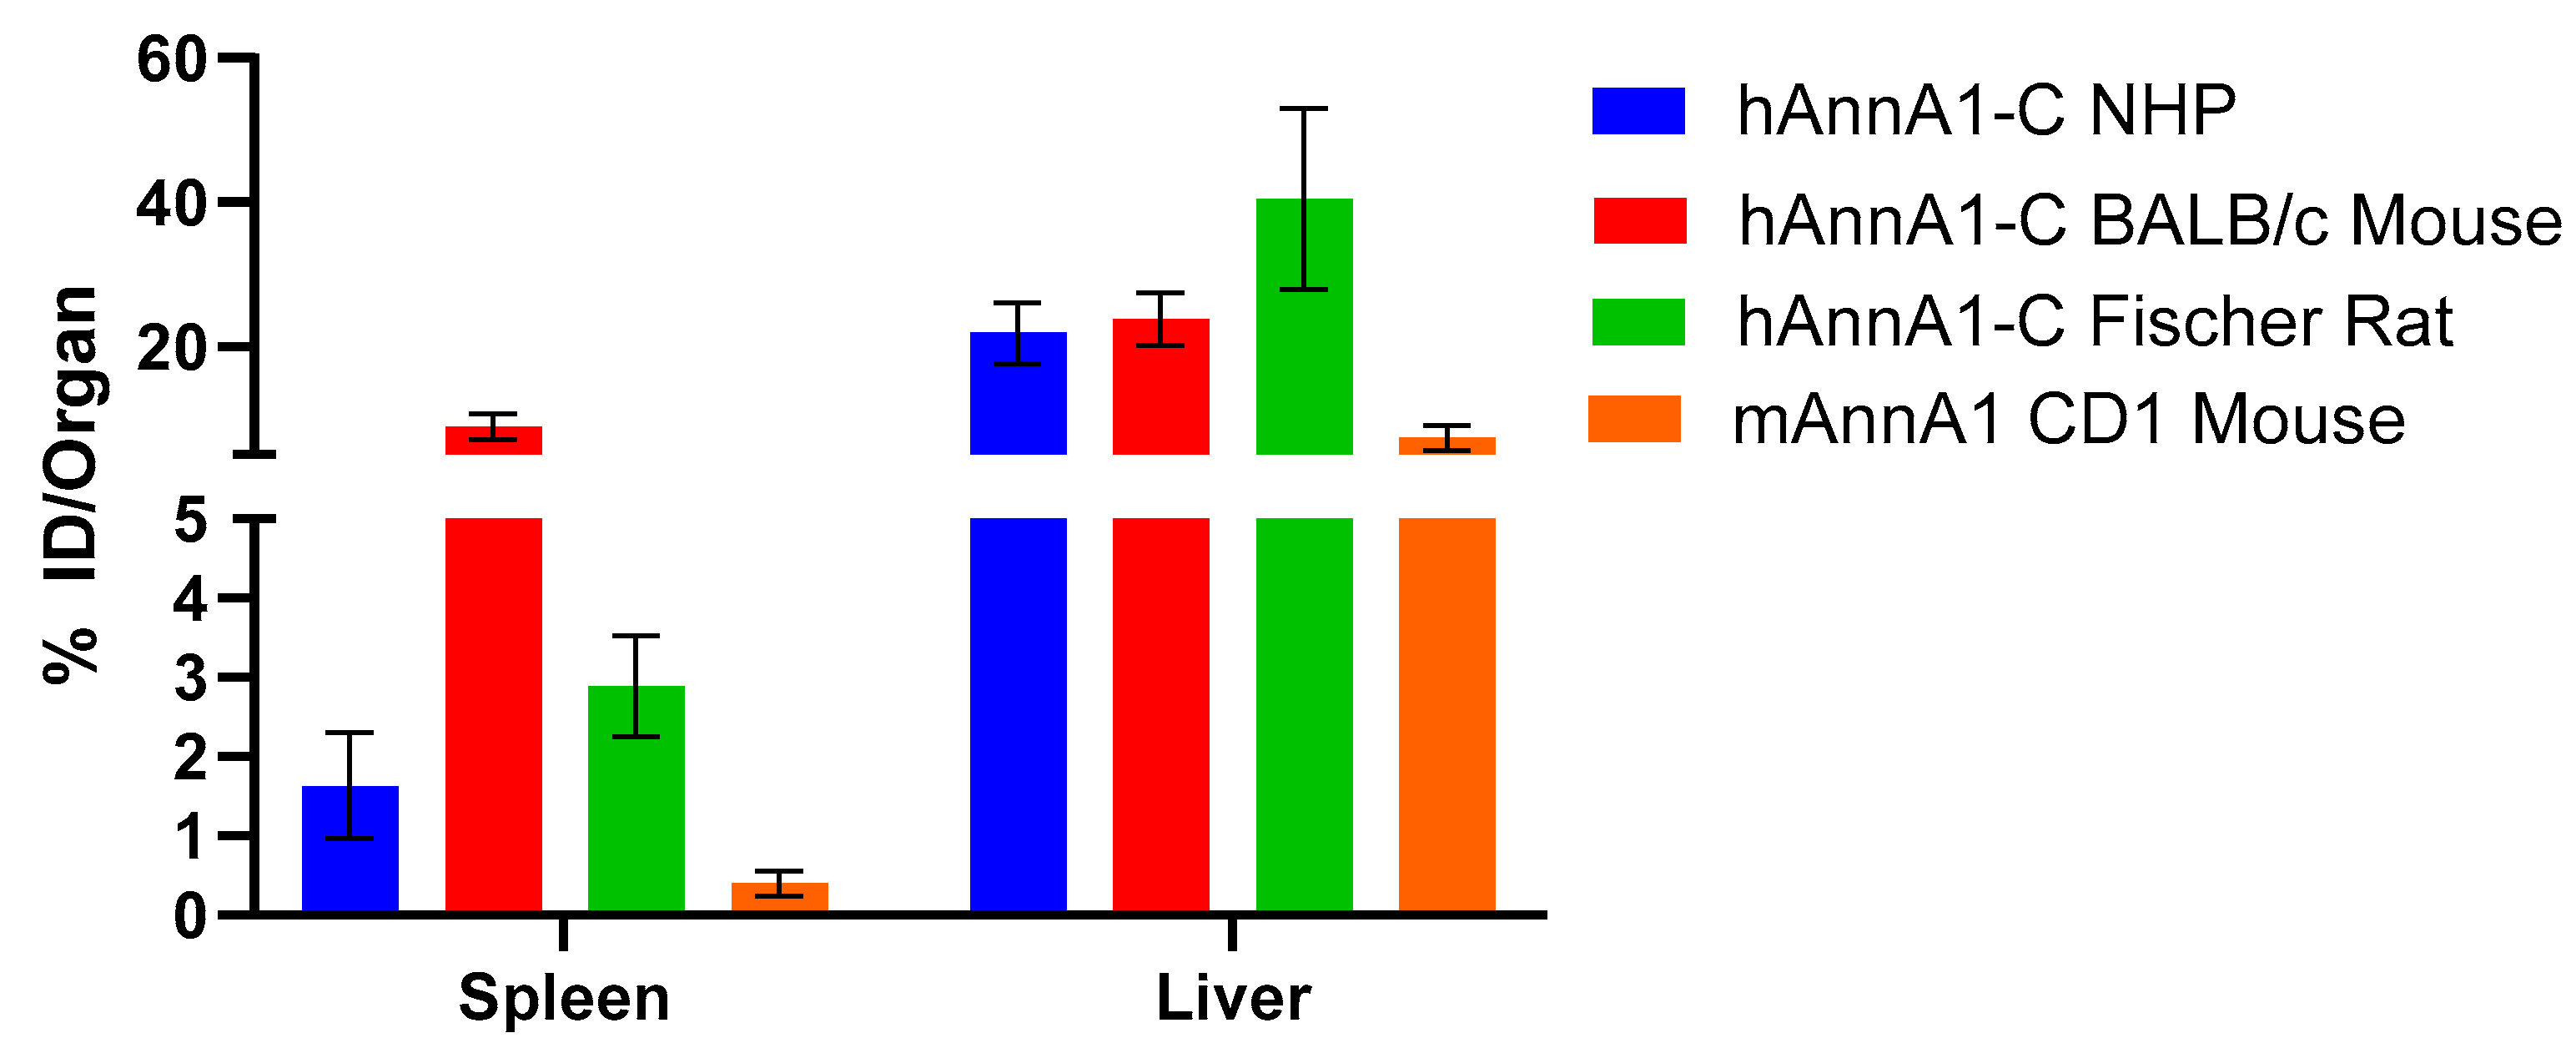

2. Results